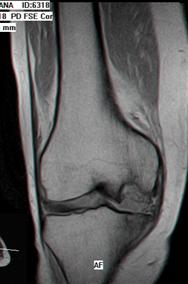

1.2.3. Rezonanta Magnetica Nucleara

Rezonanta Magnetica Nucleara (RMN) este in prezent investigatia imagistica de electie in diagnosticul si evaluarea leziunilor condrale.

Secventele standard T1 fast-spin nu sint sensibile in evaluarea leziunilor cartilajului articular, insa secventele T2 fast-spin si T1 densitate protonica cu supresie a grasimii sint atit specifice cit si senzitive in decelarea leziunilor cartilajului articular (fig. 1.5) Cea mai mare specificitate este la nivelul cartilajului articulatiei femuropatelare datorita grosimii cartilajului (fig. 1.6)

In Figura 1.9 si Figura 1.10 se pot observa leziuni de osteocondrita disecanta a condilului femural intern si extern, evidentiabile pe diferite sectiuni si secvente RMN.

Fig1.9 Imagine RMN sectiuni sagitale si transversala la nivelul genunchiului, leziune de osteocondrita disecanta a condilului femural intern |